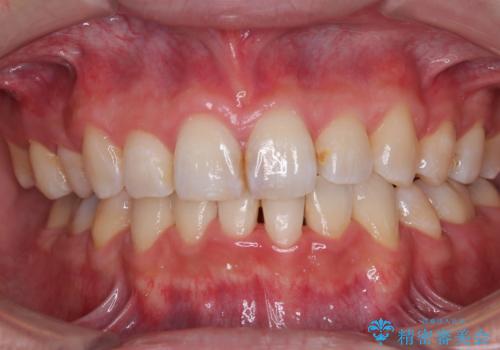

- 下顎の八重歯を気にして来院された患者様です。

左下以外、3本の第一小臼歯が既に抜去されており、左下は八重歯になっている状態でした。

左下の八重歯は手前に傾斜していたため、インビザラインによる抜歯矯正が可能と判断し、後方にある第一小臼歯を抜歯してインビザラインにて矯正治療を行うこととしました。

ワイヤー矯正と比較すると、八重歯が後方に傾斜した仕上がりとなりましたが、患者様ご希望のインビザラインにて十分な歯列を達成することができました。